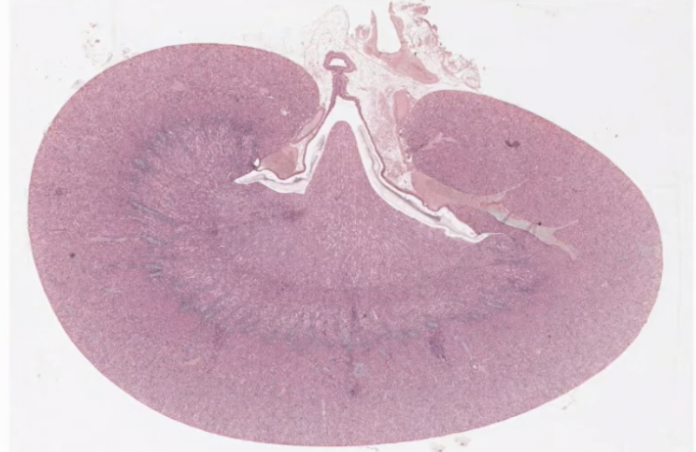

Kidney

Kidney:

Remove metabolic waste, foreign chemicals, regulate salt concentrations, and maintain blood volume and acid-base balance

Outer cortex

And inner medullary region

Renal pyramid, point/peak at renal papillae where urine drips out

Cortical tissue

Proximal distal convoluted tubules

Medullary rays and renal corpuscles

Outer renal cortex contains:

Renal corpuscle (macula densa)

Distal and proximal convoluted tubules

Medullary rays

Stripes are medullary rays (extensions of medullary projecting towards edge)

Collecting ducts and loop of henle

In between are cortical tissue